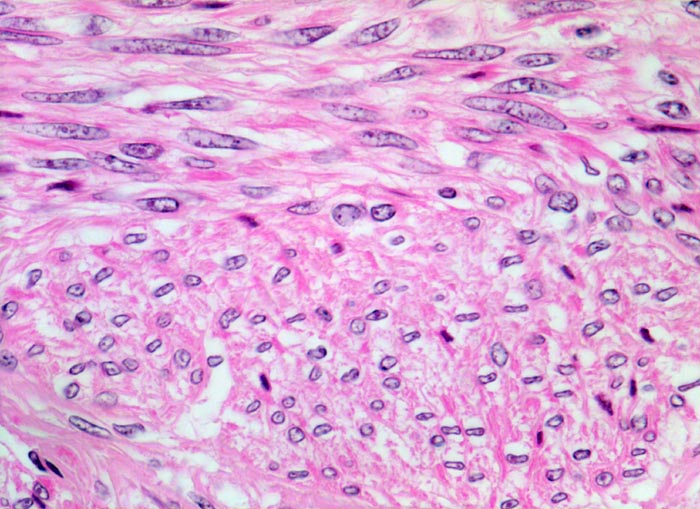

Myome imponieren makroskopisch typischerweise als runde, scharf begrenzte und nicht bekapselte Knoten. Die Schnittfläche ist weiss mit wirbliger Struktur. Mikroskopisch ist der Tumor aufgebaut aus Bündeln (=Faszikeln) spindelförmiger Zellen mit reichlich dunkel-eosinophilem Zytoplasma und an den Enden abgerundeten länglichen, zigarrenförmigen Kernen. Zell- und Fasergehalt sind sehr variabel. Degenerative Veränderungen wie Verkalkungen (> 4280), hyaline Nekrosen, Einblutungen, Homogenisierung des Kollagens, Ödem oder myxoide Degeneration und Zystenbildung (> 4279) kommen häufig vor. Manche gutartigen Leiomyome können ein einzelnes Malignitätskriterium aufweisen (vermehrte Mitosen, hohe Zellularität, deutliche Zellatypien oder Nekrosen). Falls mehr als eines dieser Kriterien vorhanden ist, handelt es sich differentialdiagnostisch um einen leiomyomatösen Tumor mit unsicherem Malignitätspotential (STUMP=Smooth Muscle Tumor of Uncertain Malignant Potential) oder um ein Leiomyosarkom. In seltenen Fällen lässt sich die Dignität nicht sicher bestimmen.

• Glatte Muskelzelle: eosinophiles Zytoplasma, längliche Kerne mit abgerundeten Enden (zigarrenförmig).

• Keine signifikanten Zellatypien. (signifikant=bereits in der Übersichtsvergrösserung erkennbar).

• Keine Mitosen.

• Keine Tumornekrosen.